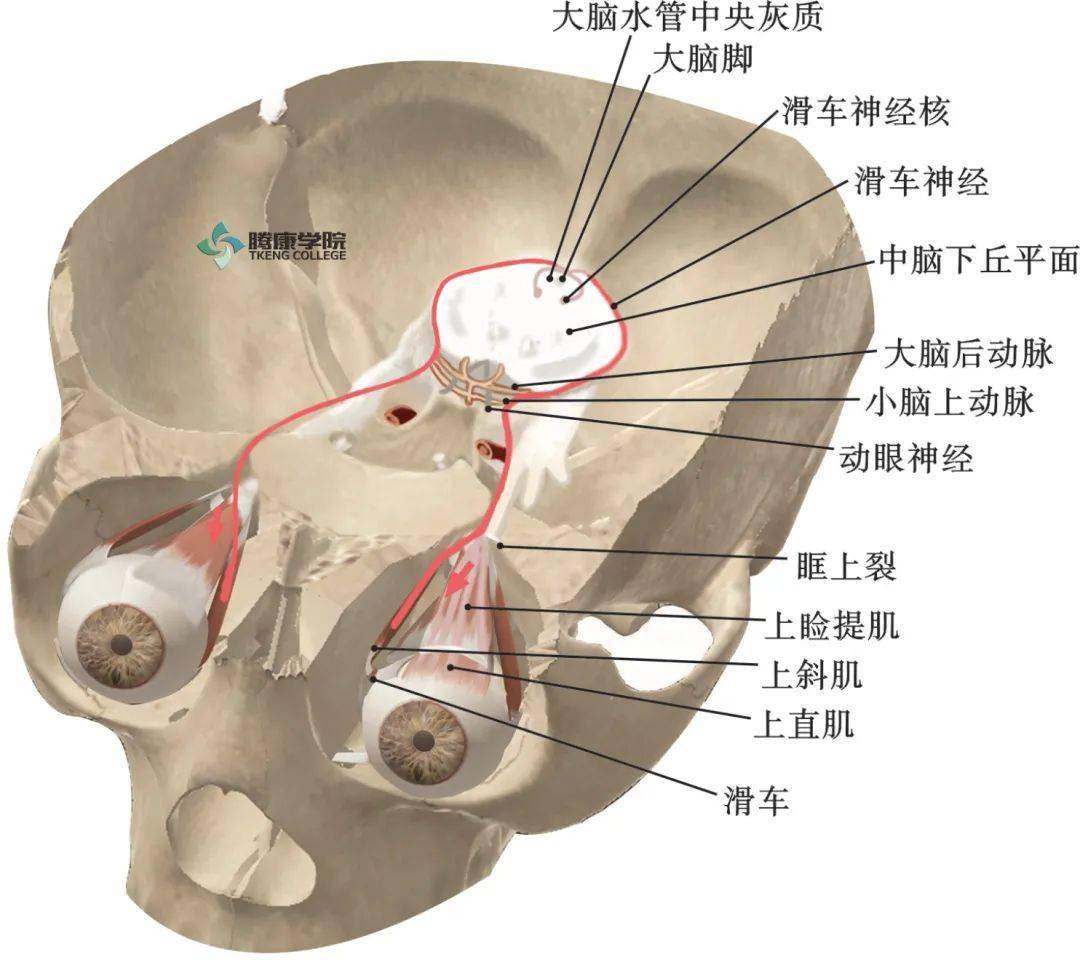

滑车神经

【图】滑车神经属于哪个神经 教你识别外展神经损伤的鉴别诊断

神经解剖外传——简单又不简单的滑车神经

海绵窦内容物:动眼神经,滑车神经从海绵窦顶壁进入海绵窦;颈内动脉在

神经解剖外传——简单又不简单的滑车神经

②切迹中间隙内主要有:pca,sca,滑车神经.

《系统解剖学》课件 Ⅳ,滑车神经 纤维成分:躯体运动纤维 行径:中